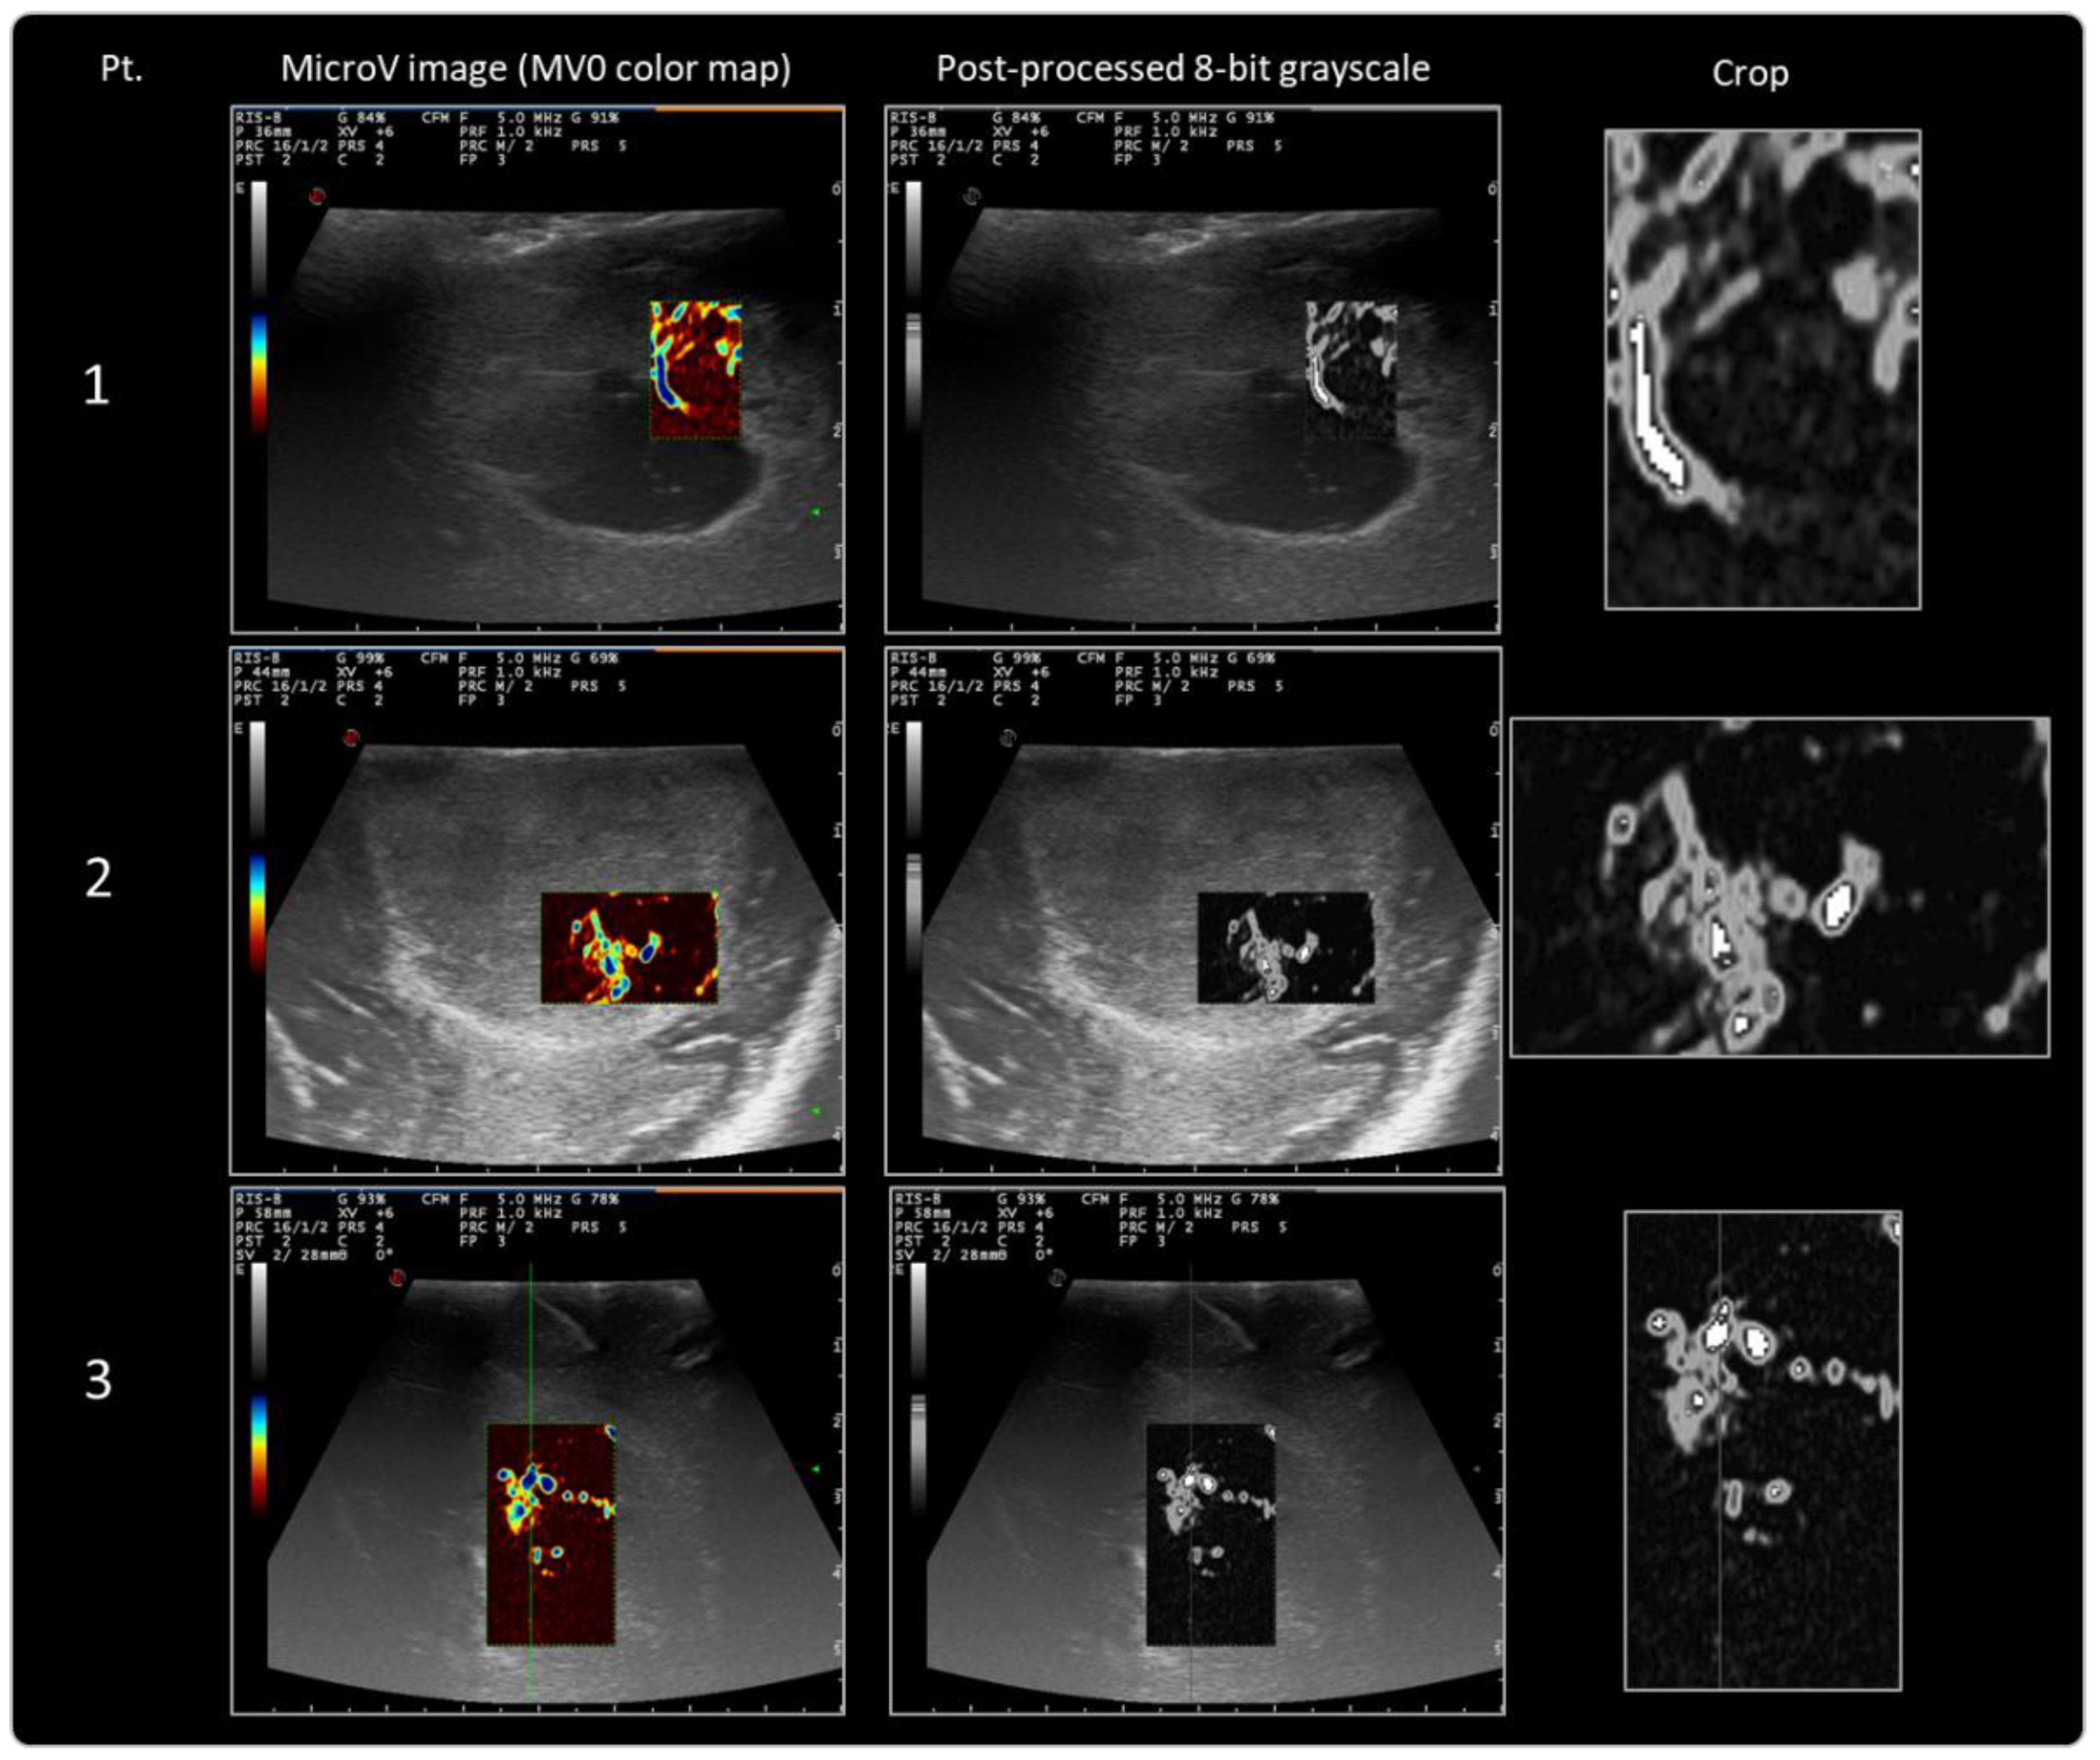

2.7.1. Post-Processing of MicroV Images

2.7.2. First-Order Radiomic Analysis

Protocol Refinement and First Proof-of-Concept Applications